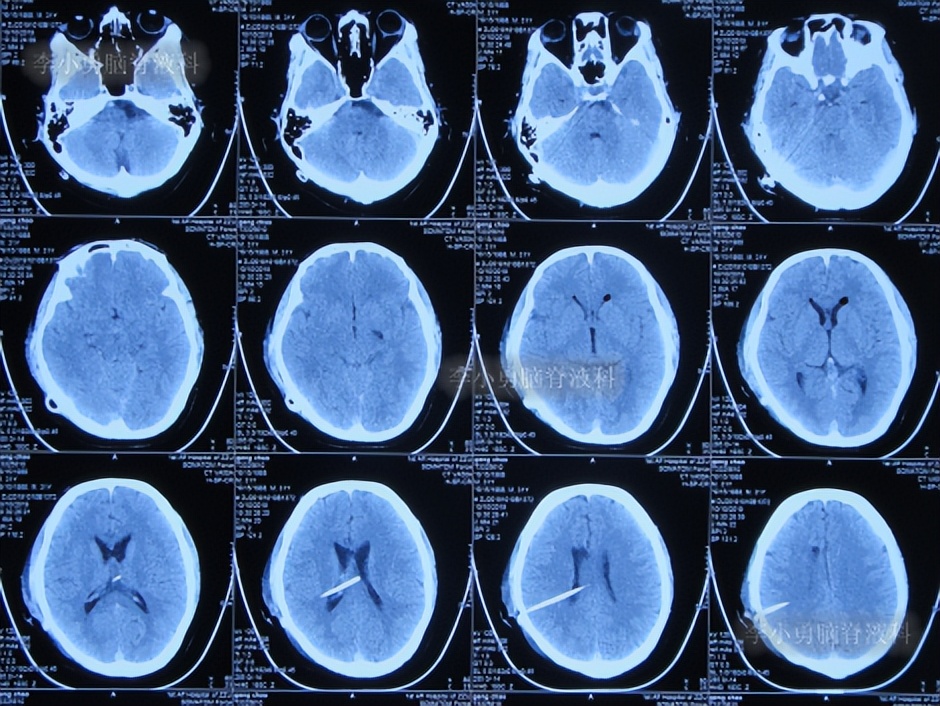

第3次出院后24天即2019年11月10日,因视物又出现模糊,在当地医院查头颅CT示脑室又有扩张(图-4),给予手术的医生建议继续观察。

图-4:2019年11月10日头颅CT